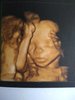

Hej dziewczyny, ja ostatnio nawet nie mam kiedy nadrobić.. cały czas coś się dzieje teraz wreszcie chwila relaksu nad morzem i staram się nie zerkać w ogóle na telefon. Przed wyjazdem zaliczone połówkowe, wszystko super oprócz jasnej plamki na serduszku ale pani doktor mówi że tym się nie przejmować to nie wada i zapewne samo zniknie. 20+4 młody ważył 380g. Pozdrawiamy!